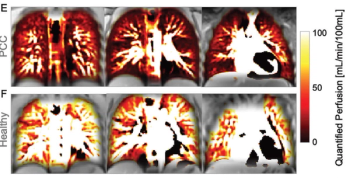

Adolescents with post-COVID-19 conditions had 37 percent lower quantified lung perfusion than healthy control participants on phase-resolved functional lung MRI, according to findings from a recent prospective study.